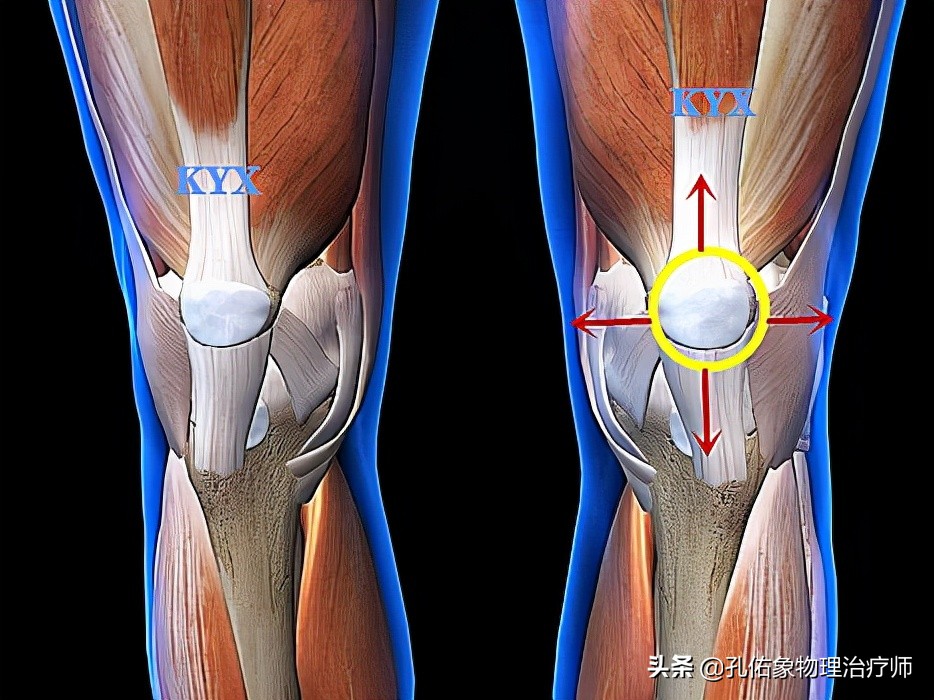

主要是长在骨头上的肌肉和韧带。在膝盖的四周都有不同的肌肉、韧带,从不同的角度发力来维持膝关节和膝盖骨的稳定;倘若哪一侧太弱,其他侧太强,就会打破原有的稳定状态,出现不同的腿型、不同方向的膝盖骨移位。

正常情况下 ,如动图所示,在您屈膝(弯腿)的时候,膝盖骨(俗称菠萝盖)会往内下方移动;而伸膝(伸腿)的时候,膝盖骨会往外上方移动。

倘若您的腿型不正常(往往没有人给您分析评估,易被认为是正常的),如您存在X型腿或O型腿,每天都要行走、跑跳、下蹲,必然要弯腿和伸腿,不知不觉发生膝盖骨的异常活动,即运动的 轨迹不正常 ,将会导致膝盖骨和大腿骨之间产生不正常的应力刺激,引发疼痛。

一般弹响和膝盖骨的位置运动密切相关;比如说,您的膝盖骨已经靠近膝关节的外侧了,在弯腿的时候,它往内下移动不够,就会在膝盖骨和大腿骨之间摩擦发生弹响。反之,在伸腿时,也是同样的道理。